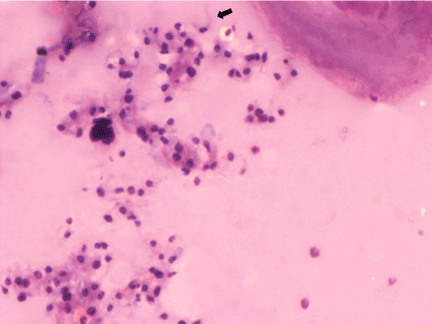

| Figure 2: Freeze dry section of a leech, thirty minutes after the infective blood feeding with Trypanosoma evansi. In the coelomic cavity are seen several clusters of trypanosomes localized in the anterior region of the leech close to the proboscis. Note several rounded forms together to trypomastigotes (arrow) (2.300 X). |